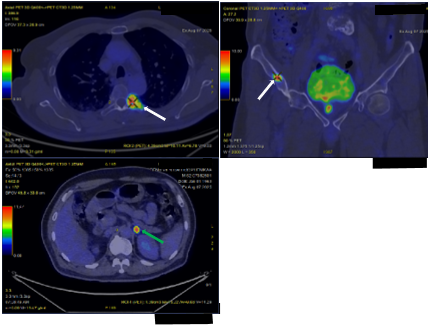

Sau đó, bệnh nhân được chụp PET/CT toàn thân, một phương pháp y học hạt nhân hiện đại, rất có giá trị trong phát hiện các tổn thương, đặc biệt là các tổn thương di căn hạch và di căn xa. Phim chụp cho thấy bệnh nhân có rất nhiều tổn thương tại nhu mô phổi hai bên, tại tuyến thượng thận trái, tại xương nhiều vị trí và tại tuyến tiền liệt, tăng hấp thu FDG thể hiện tính chất ác tính (Hình 5).

Hình 5: Hình ảnh PET/CT cho thấy: 02 khối u phổi phải, kích thước lớn nhất 16 x 23 mm, xâm lấn vào trung thất (SUVmax: 17,8) và các nốt đặc nhỏ rải rác nhu mô hai phổi, tăng hấp thu FDG (SUV: 10,5) (mũi tên đỏ). Hình ảnh các tổn thương tại xương (mũi tên trắng) tương ứng với các vị trí tổn thương quan sát thấy trên xạ hình xương (SUVmax: 22,2). Hình ảnh nốt tuyến thượng thận trái(mũi tên xanh), tăng hấp thu FDG (SUVmax: 15,2). Hình ảnh tăng hấp thu FDG tại vùng chuyển tiếp,vùng ngoại vi bên phải tuyến tiền liệt và thành dưới bàng quang (SUVmax: 17,1) (mũi tên vàng).